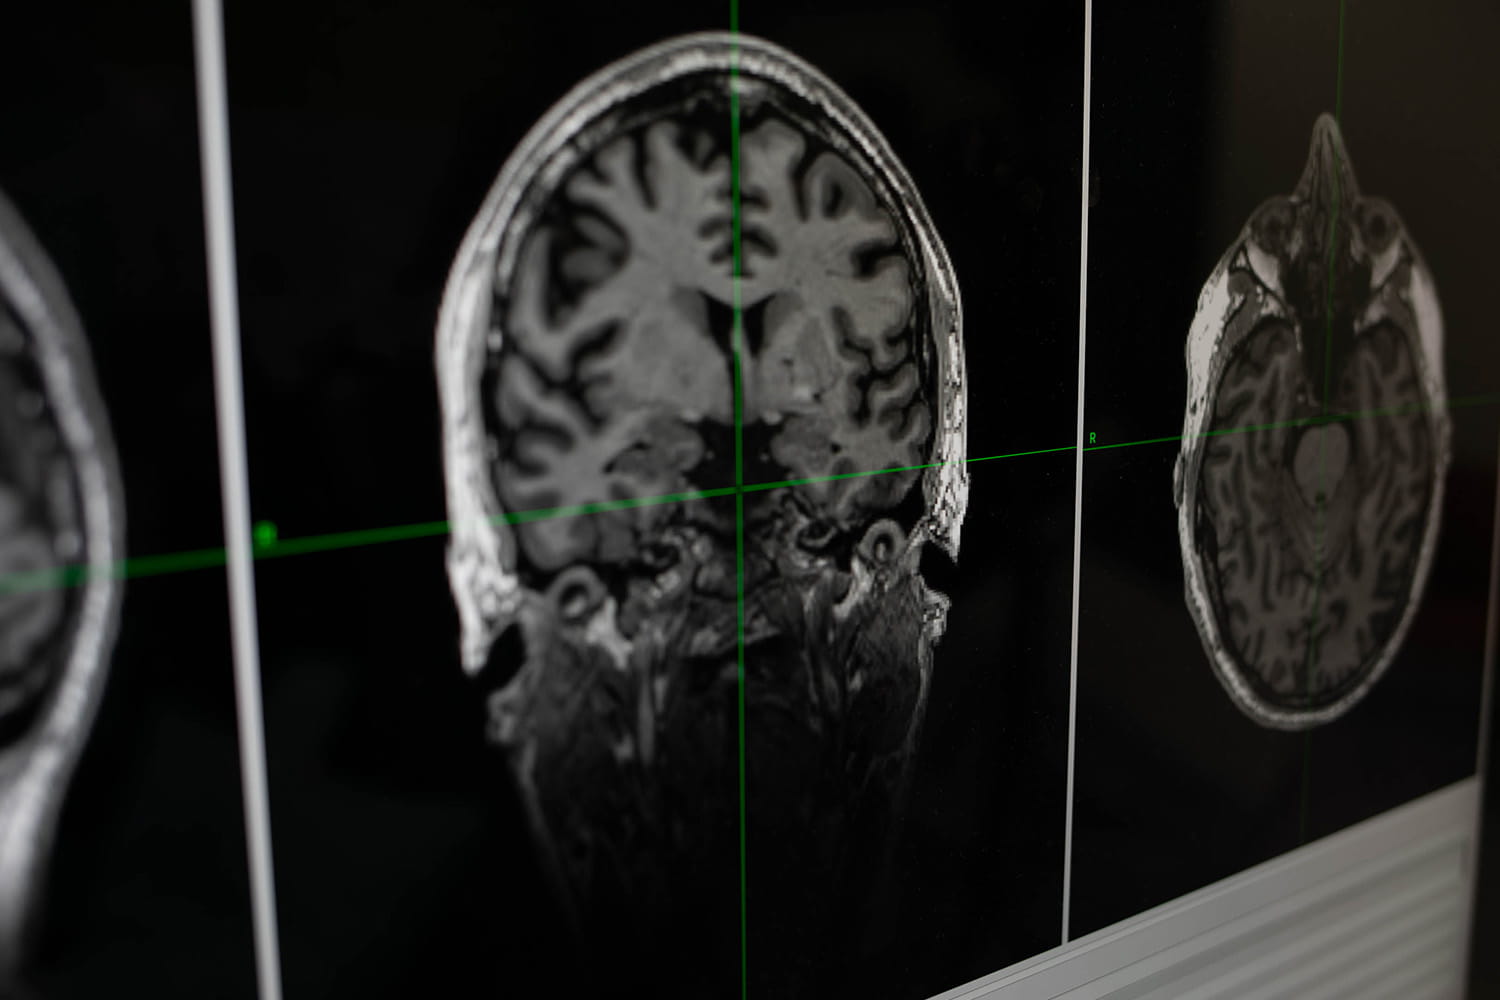

The breakthrough lies in the delivery mechanism. While ECT sends an electrical current through the brain to induce a therapeutic seizure, MST utilizes targeted magnetic stimulation. This allows clinicians to trigger the necessary seizure activity to reset neural pathways while strategically avoiding the brain regions most responsible for memory. By isolating the therapeutic effect from the cognitive damage, researchers at CAMH and UC San Diego have effectively decoupled the cure from its most debilitating side effect.